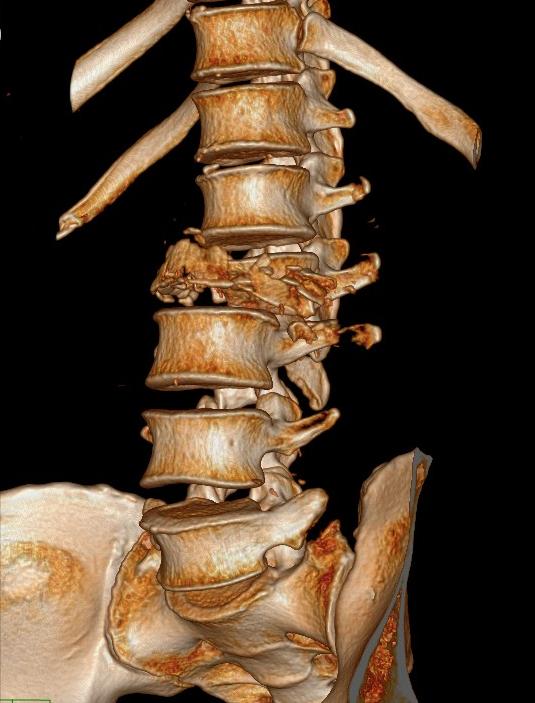

诊断为:1、 腰2椎体爆裂性骨折伴截瘫

腰椎骨三维重建